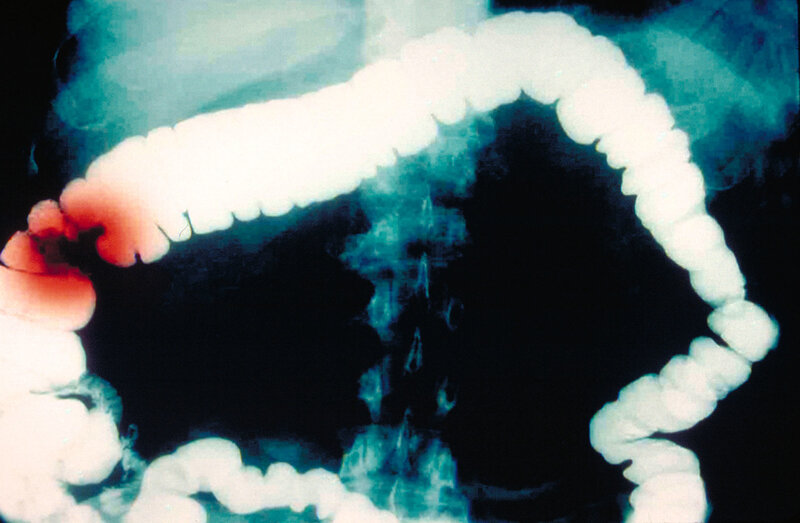

Colon Cancer's Up Among Gen Xers And Millennials, But Scientists Say Reasons Are Elusive

One of the great treats of following an Agatha Christie mystery (my favorite being Hercule Poirot) is that you know there will be an "Aha!" moment at the end. The fastidious, mustachioed detective will pull together all the disparate facts and present a compelling answer. I'm frequently reminded that science doesn't work that way. The latest case in point is an article published Tuesday in the Journal of the National Cancer Institute that sets out to explore a trend in colorectal cancer among younger Americans....